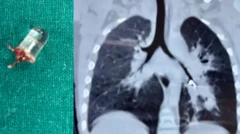

3 ਸਾਲ ਦੇ ਮੁੰਡੇ ਦੇ ਫੇਫੜਿਆਂ ਵਿੱਚੋਂ ਕੱਢਿਆ ਗਿਆ ਐੱਲਈਡੀ ਬਲਬ, ਜੇਕਰ ਬੱਚਾ ਸਿੱਕੇ, ਬੈਟਰੀ, ਚੁੰਬਕ ਵਰਗੀ ਚੀਜ਼ ਨਿਗਲ ਜਾਵੇ ਤਾਂ ਕੀ ਕਰਨਾ ਚਾਹੀਦਾ ਹੈ